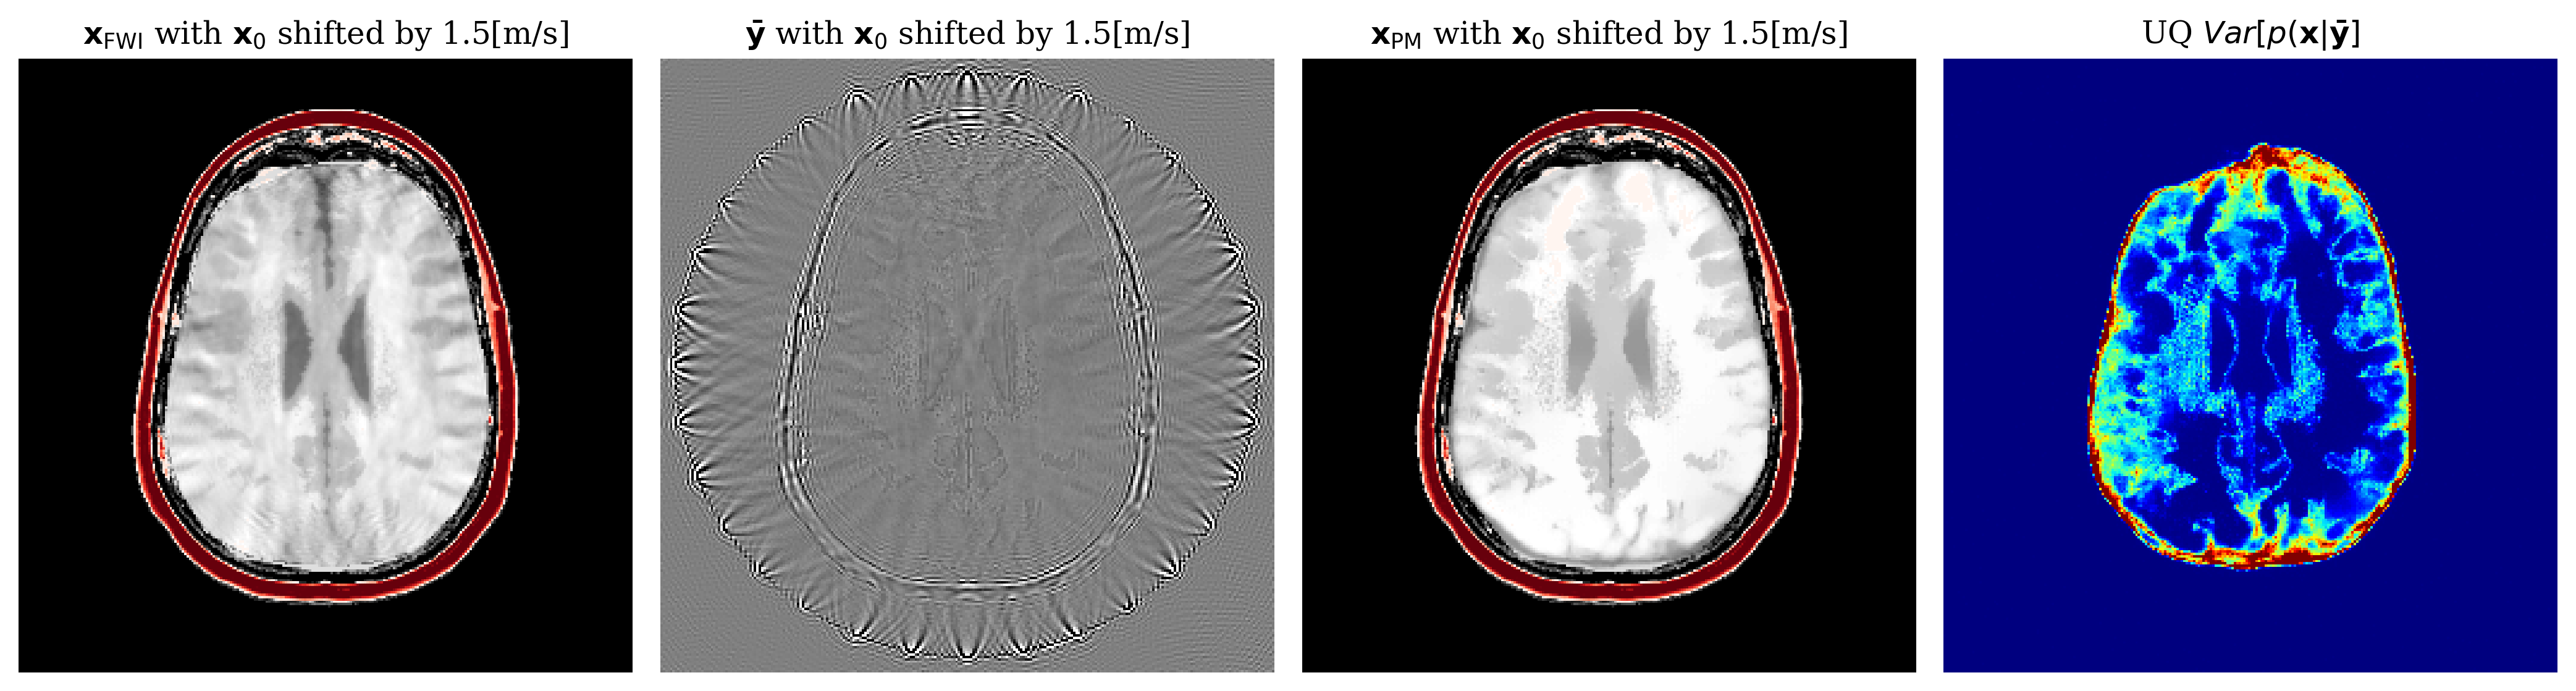

We highlight that our method assumes access to good starting points . In Appendix 4.5 we show that as this starting point gets worse then the physics-informed summary statistic fails to inform the posterior. This results in degradation of the samples. We see this result as a quality assurance since our generative model does not falsely generate realistic but wrong samples. This is a limitation of gradient approaches in nonlinear problems as demonstrated by FWI also failing for the poor starting points Appendix \figurereffig:shift05. In future works, we would like to find ways to be robust against poor starting points.

We study the effect of this starting model on the result of our method by adding a constant shift to the constant velocity inside the skull of the starting model. Unsurprisingly, our method degrades in quality as the starting point degrades \figurereffig:shift05. This behaviour is expected and unavoidable since our method is gradient based and nonlinear. As evidenced by failure of FWI \figurereffig:shift05, this is a limitation to methods that use gradients.

fig:shift01

fig:shift05